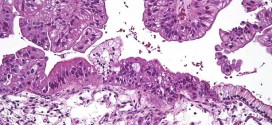

CARCINOMA VILIFORME DE LA CAVIDAD ORAL

El carcinoma viliforme de la cavidad oral. Durante los primeros años de vida de una persona, las células normales se dividen más rápidamente para permitir el crecimiento. El cuerpo está compuesto por billones de células vivas. Las células normales del cuerpo crecen, se dividen formando nuevas células y mueren de manera ordenada. Una vez que se llega a la edad …